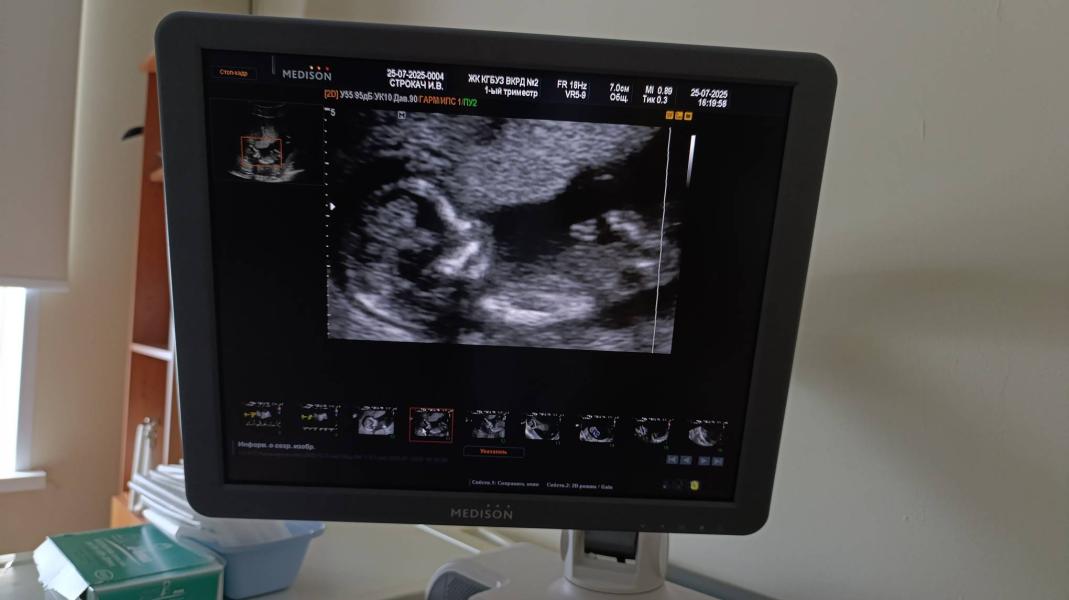

Спал малышок. Ножки крестиком, ручки у лица. Замечаний нет. Сердцебиение 154. На 25 июля срок 13 недель и 4 дня. Сейчас дату ПДР не ставят, удивили. Врач спросила "понравился ли он мне"🫶

Теперь ждём анализ крови🤞